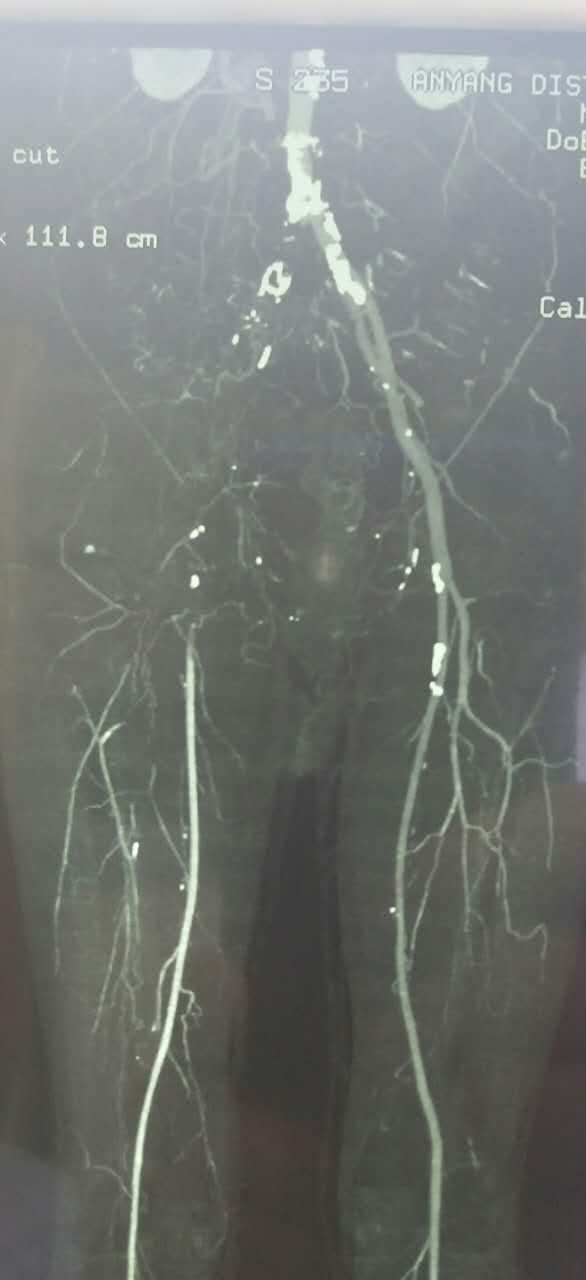

入院后,结合病史,考虑有血栓形成的可能性,行全身静脉溶栓,一周后复查CT,右侧髂总动脉出现一段管腔

对比正常解剖模式图,我们可以发现:右侧髂总髂内髂外股总动脉未显影,股深动脉未显影,右侧股浅动脉起始段未见显影,考虑有血栓闭塞的可能。